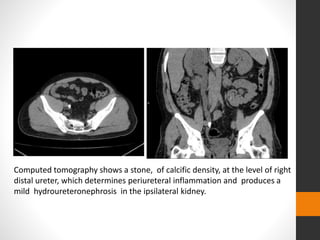

Computed tomography shows a stone, of calcific density, at the level of right

distal ureter, which determines periureteral inflammation and produces a

mild hydroureteronephrosis in the ipsilateral kidney.